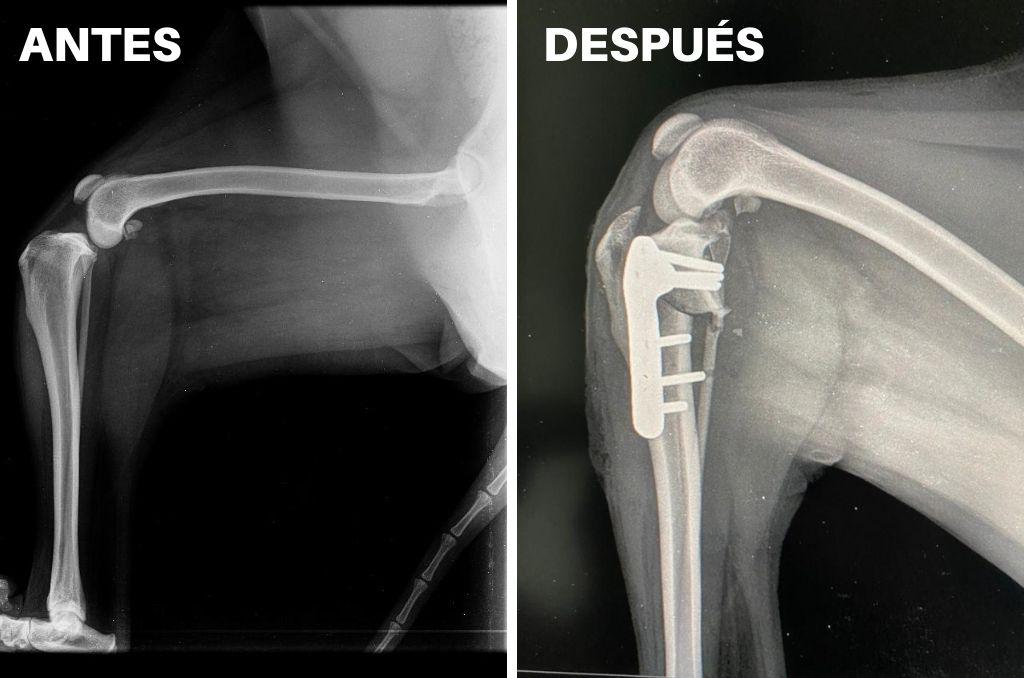

Una intervención pionera en el ámbito veterinario de Iquique, realizó el cirujano y diplomado en Medicina Interna, Arthur Schütte, quien junto a un grupo de profesionales locales ejecutó la primera osteotomía niveladora del plato tibial reconocida como TPLO.

La intervención fue realizada en el pabellón principal de la clínica ZooMundo y permitió solucionar la rotura del ligamento cruzado anterior de Peppa, una Golden Retriever de cinco años.

“La TPLO es una cirugía abreviada que busca nivelar el plato tibial, la que se transforma en la solución más moderna que se puede realizar cuando el perrito corta el ligamento cruzado craneal”, explicó Schütte, advirtiendo que en lo medular la operación busca cambiar el ángulo del plato tibial.

“Esta técnica permite restablecer la estabilidad de la rodilla y modificar de tal manera el aspecto que no se requiere intervenir el ligamento, pues gracias a la torsión y la placa instalada, ya no se necesita de un ligamento”, dijo el médico proveniente de Linares, quien agregó que este tipo de dolencias invalidantes para los caninos se puede producir como consecuencia de traumas o de procesos degenerativos en la articulación de las rodillas.

“Peppa, quien fue intervenida hace dos años por problemas similares en la extremidad derecha, llegó a ZooMundo sin apoyar su pata, con un indicador grado cuatro que le causaba mucho dolor, pero afortunadamente con esta intervención que se transforma en la primera que se ejecuta en la región, va a poder tener una recuperación rápida”, detalló Franco Delucchi, médico veterinario y director de ZooMundo.

Agregó que “en una semana el paciente podría estar caminando con un pequeño grado de cojera, pero al mes ya debiera caminar con absoluta normalidad”, argumentó Delucchi, quien mencionó que este tipo de cirugías solo las había visto en videos y en las charlas realizadas por el mismo Schütte, quien además es vicepresidente de la Sociedad Chilena de Traumatología y Ortopedia Veterinaria. ¡Viva Iquique!